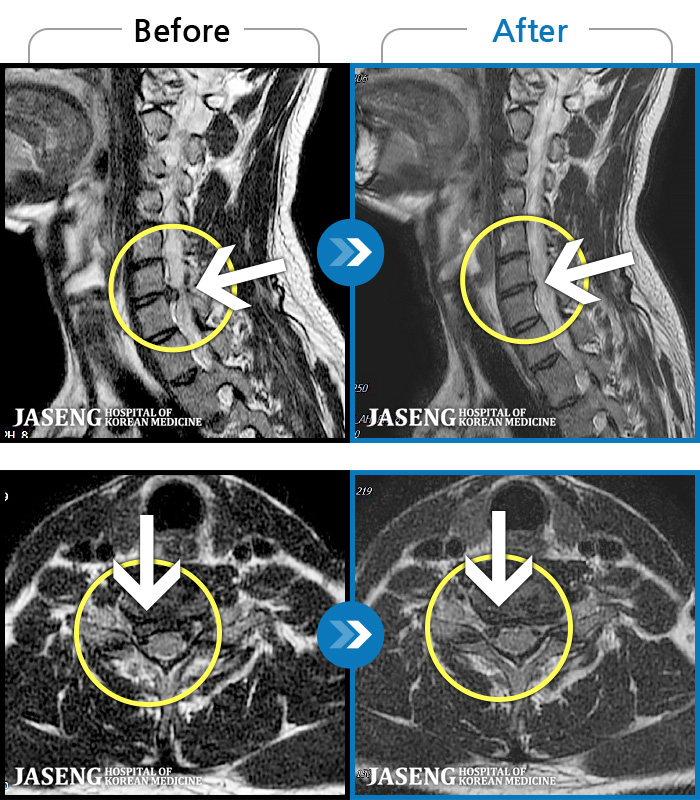

목디스크

인천 · 조남훈 원장

증상이 재발하였습니다.

촬영시기

2021.11.20 ~ 2025.11.13

2025.11.21

조회수 131